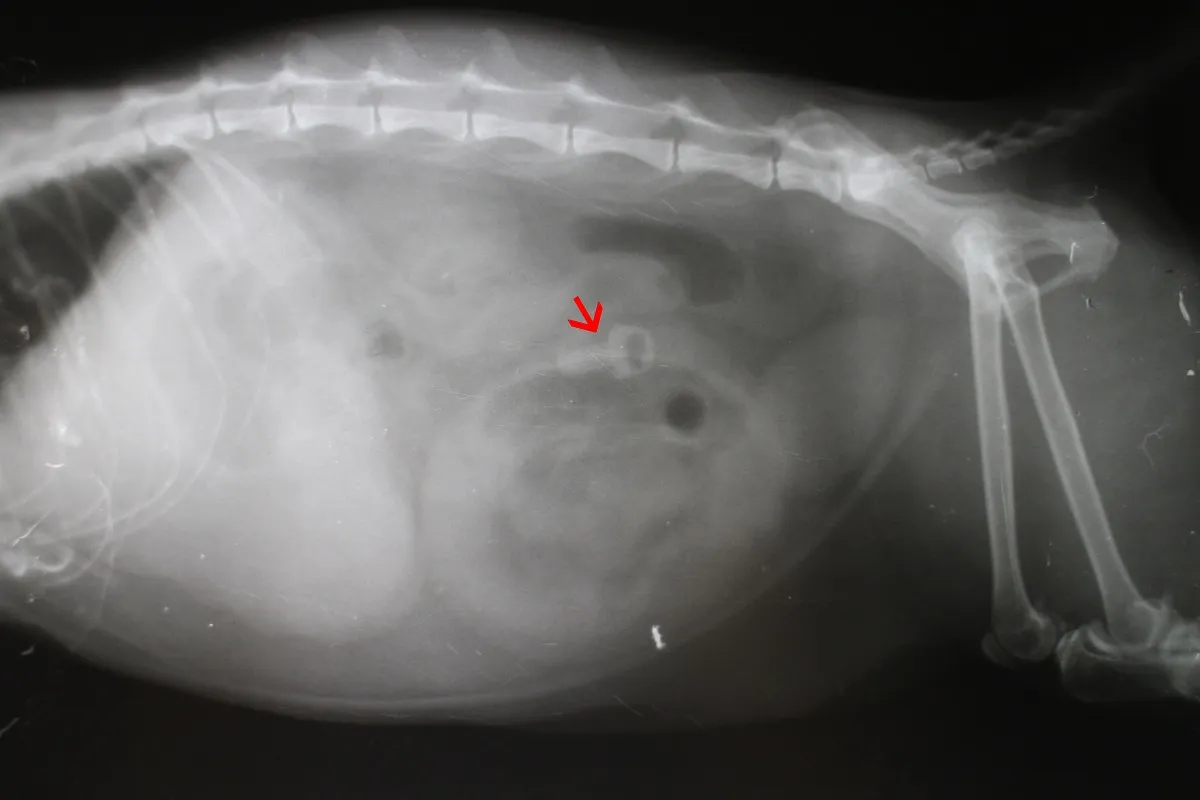

Zusätzlich kann er Ihren Schmuser auf weitere Grunderkrankungen untersuchen und Fremdkörper mittels bildgebender Verfahren (z. B. Röntgen) sichtbar machen.

Der rote Pfeil auf dem Röntgenbild markiert einen unverdaulichen Fremdkörper im Darm einer Katze.